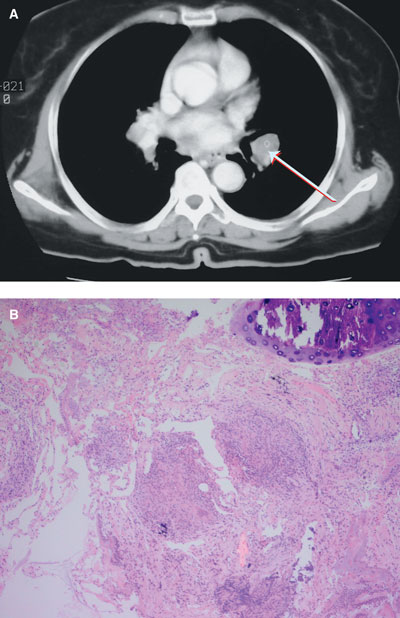

No abnormality was detected on chest x-ray or brain magnetic resonance imaging. However, a computed tomography scan of the chest showed bilateral hilar lymphadenopathy with bilateral basilar lung infiltrates (Box, A). A transbronchial biopsy revealed a single, non-caseating granuloma (Box, B).

This is an unusual case of sequential or “consecutive” bilateral facial paralysis — in which unilateral facial palsy was followed by contralateral facial palsy before the side affected first had recovered — in association with biopsy-proven pulmonary sarcoidosis. This case makes the point that a normal chest x-ray does not, unequivocally, exclude hilar lymphadenopathy.